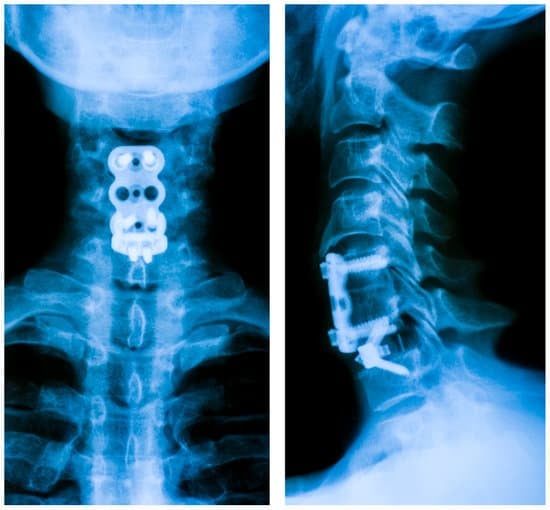

✅ 경추 유합술(Cervical Fusion)은 경추(목뼈)의 불안정성을 치료하기 위해 두 개 이상의 척추 뼈를 고정하는 수술입니다.

✅ 금속 나사(스크루), 플레이트, 뼈 이식 등을 활용하여 척추를 단단히 고정하고, 신경 압박을 완화하는 것이 목표입니다.

✅ 1) 전방 경추 유합술(ACDF, Anterior Cervical Discectomy and Fusion)

✔ 목 앞쪽(전방)에서 접근하여 디스크를 제거하고, 척추를 고정하는 방법

✔ 인공 디스크 또는 뼈 이식물을 삽입하여 유합

✔ 신경 압박 해소 & 척추 정렬 교정에 효과적

📌 디스크 문제, 척추관 협착증 치료에 가장 많이 사용되는 방법

✔ 목 뒤쪽(후방)에서 접근하여 척추를 고정

✔ 금속 나사(스크루)와 봉을 사용하여 안정화

✔ 척추 불안정성, 골절, 변형 교정에 효과적

🔹 Step 3: 뼈 이식 또는 인공 디스크 삽입 → 척추 고정

🔹 Step 4: 나사(스크루) & 금속 플레이트로 고정